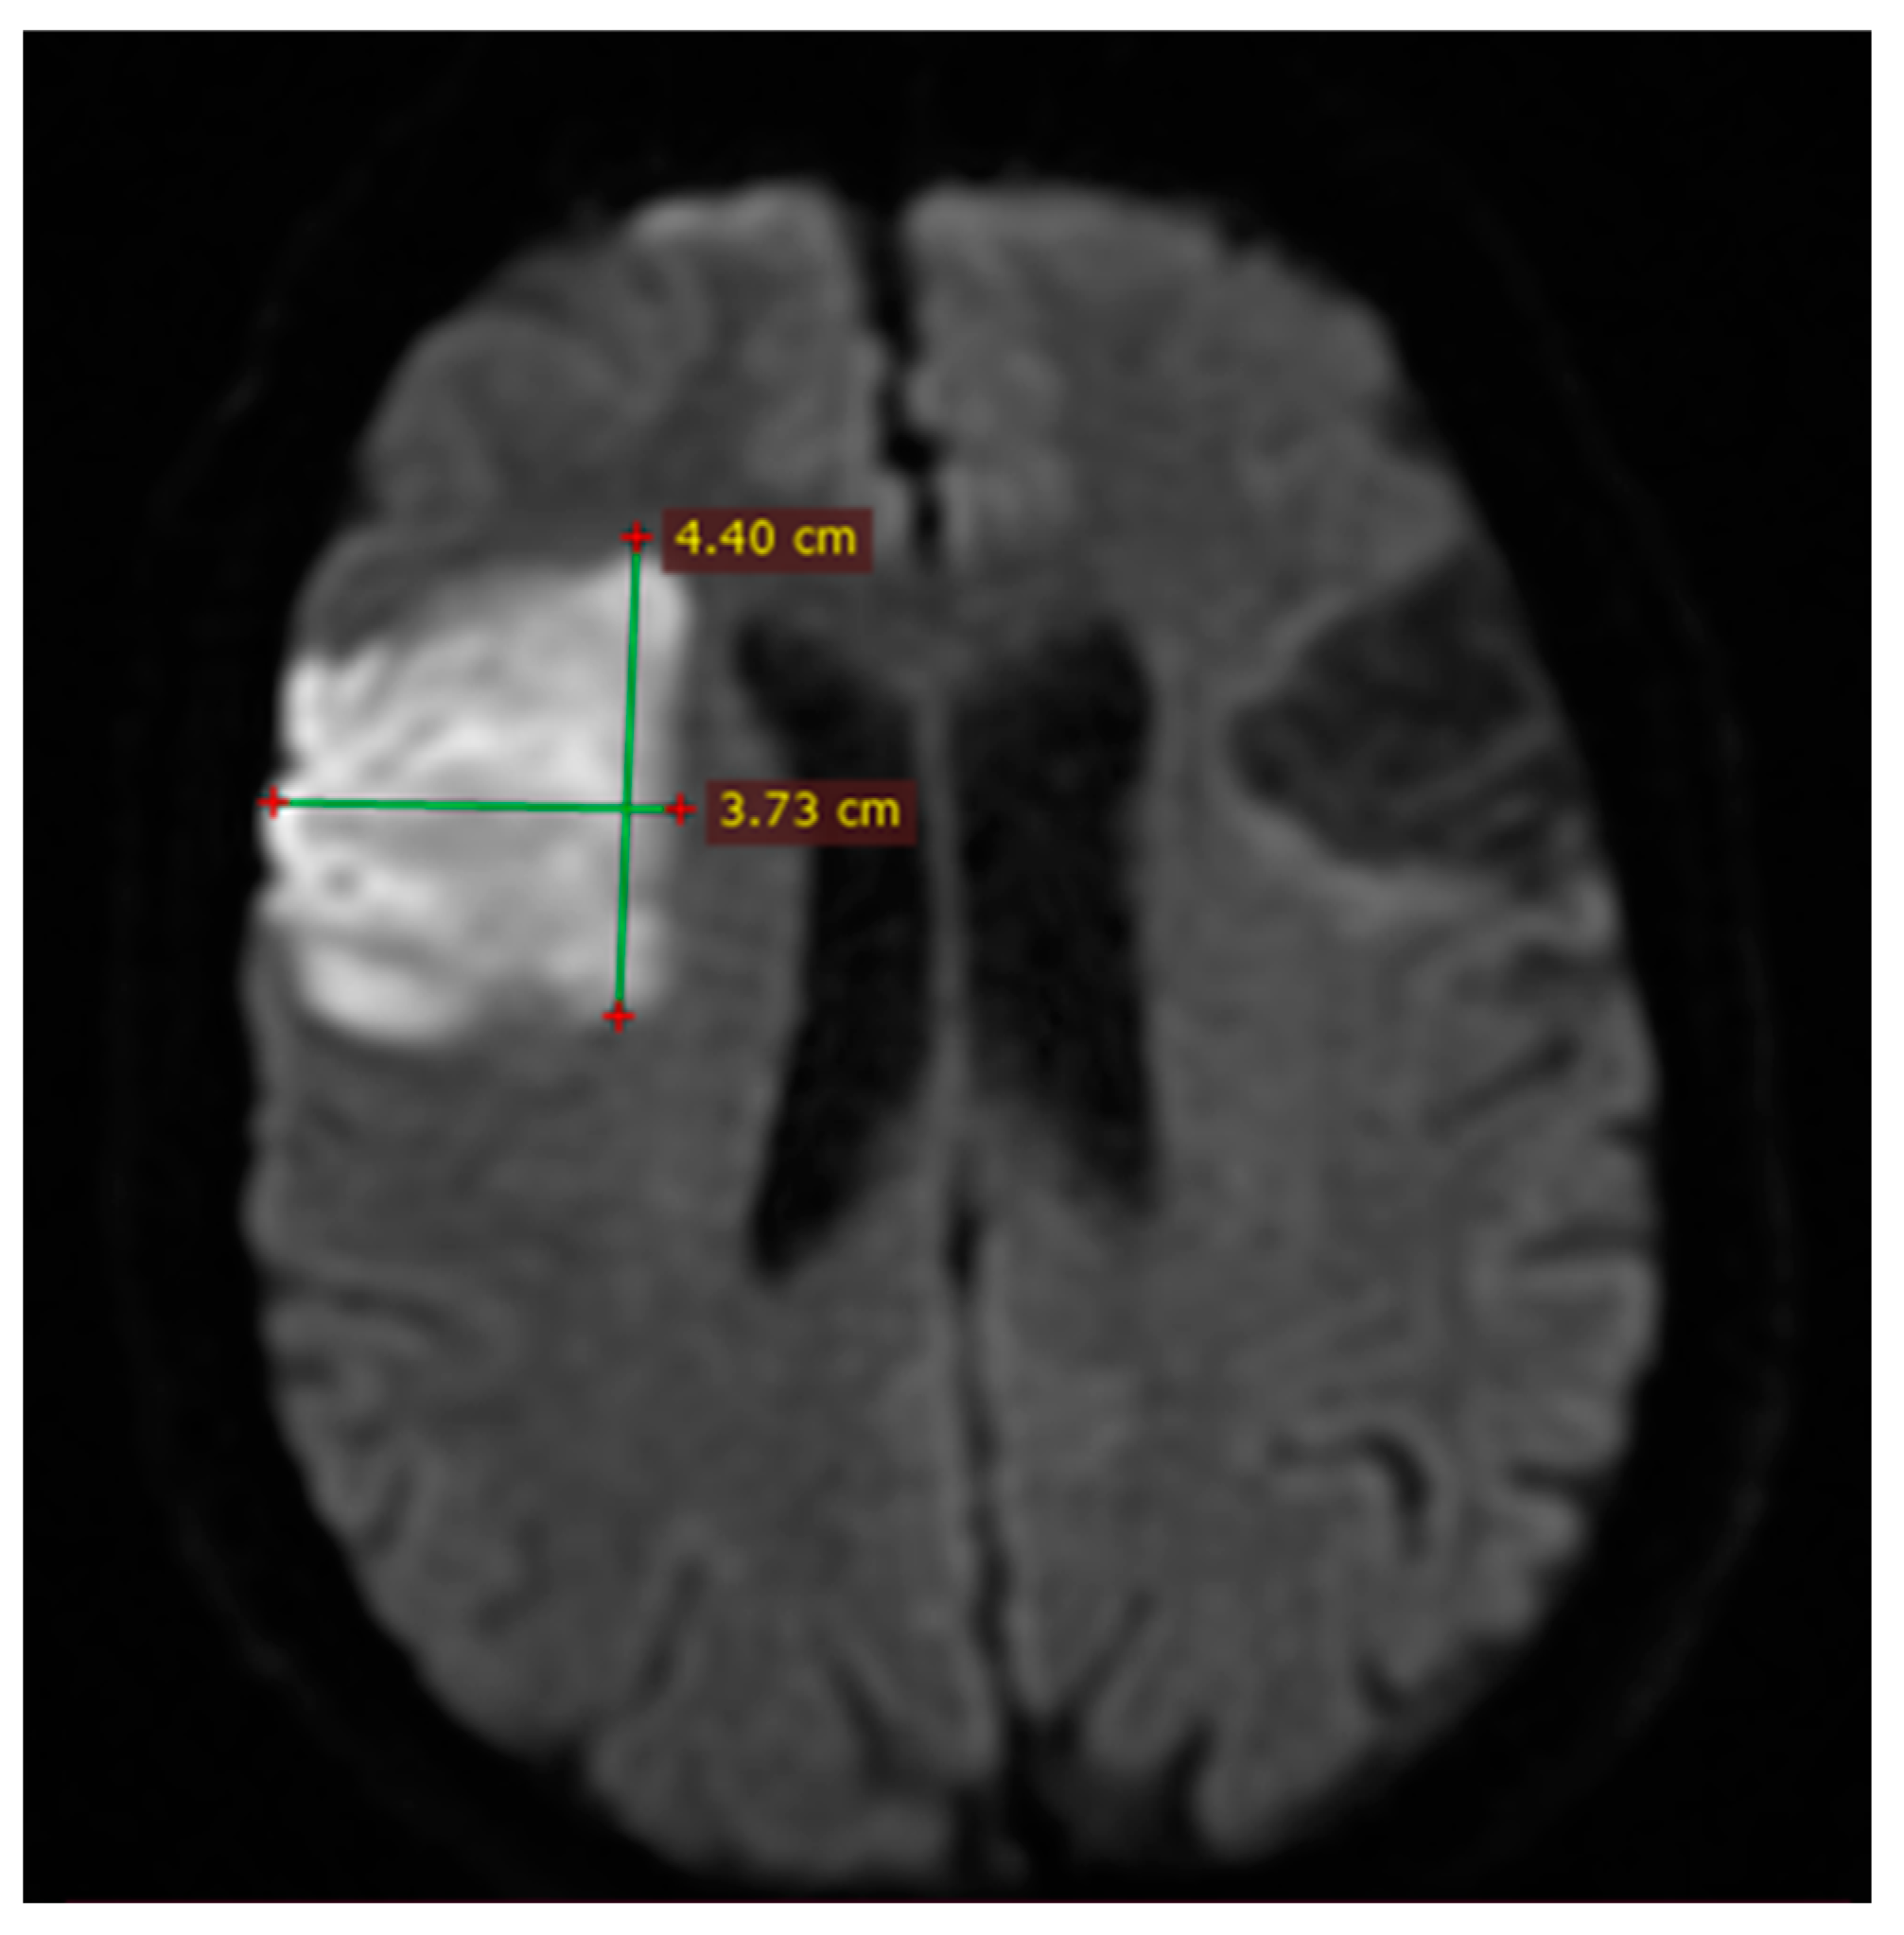

2.6. Imaging and Clinical Assessment